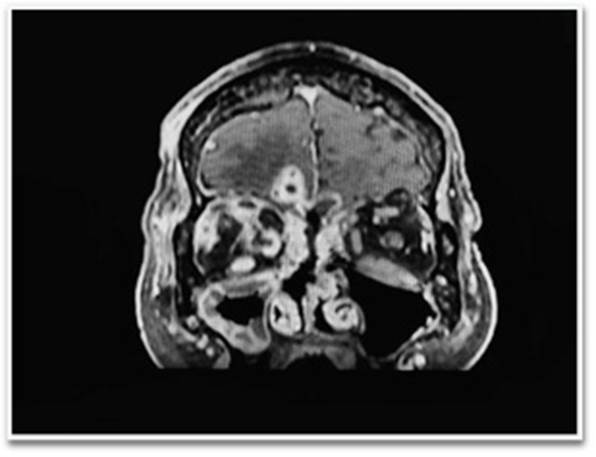

La imagenología craneal es fundamental para el diagnóstico, la tomografía computarizada con contraste es utilizada para determinar el tamaño y numero de los abscesos, aunque no puede determinar entre metástasis o tumores cerebrales primarios. Además de este, la resonancia magnética también es una valiosa herramienta de diagnóstico para así poder diferenciar el absceso cerebral primario, quístico o tumores necróticos (Figuras 4 y 5).

Figura 4 SPGR con gadolinio, secuencia coronal, en el que se observa reforzamiento regular de las lesiones, así como reforzamiento paquimeníngeo frontonasal y una sinusitis frontoetmoidal, con afectación de los músculos rectomedial derecho y oblicuos superiores.